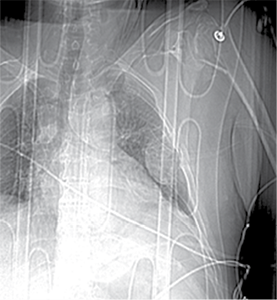

Figure 3. X-ray after shoulder arthroplasty

In a subsequent consultation, it was decided to perform shoulder arthroplasty 11 days later using reverse prosthesis (Delta Xtend, DePuy Synthes) with tuberosity fixation.

Postoperative course was uneventful in the chest or shoulder. The patient was discharged after 23 days from admition.